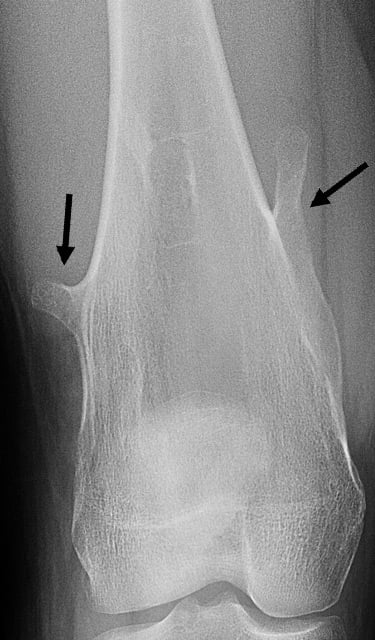

Osteochondromas, whether single or multiple, can be described as pedunculated (a narrow stalk of bone), or sessile (broad base of bone).

Anteroposterior (Front-to-back) X-ray image showing multiple, pedunculated osteochondromas on a femur.